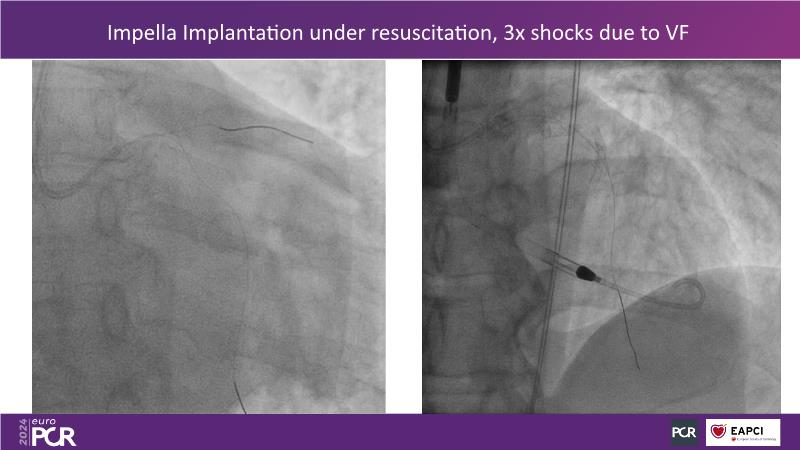

This session is essential for those looking to analyze and discuss the findings of the DanGer shock randomized trial, explore the latest evidence in the ACS field such as Horizon, and implement evidence-based practices in peri-procedural planning, execution, drug administration, and weaning strategies to optimize outcomes in acute myocardial infarction complicated by cardiogenic shock, since the session presents the latest data on ECLS and Impella, compares both in shock management, and offers insights on improving survival rates in shock patients, including the latest data on revascularization completeness with percutaneous ventricular assist devices versus IABP.

- To learn the latest data on ECLS, Impella and comparison of both in shock